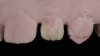

A 16-year-old female patient presented with the chief complaint that she was dissatisfied with the appearance of her anomalous maxillary lateral incisors (teeth Nos. 7 and 10) and multiple diastemas (Figure 1 through Figure 4). She had been referred for restorative treatment after an initial consultation with the orthodontist. Her first restorative appointment was dedicated to data collection, which included a health history and physical examination as well as the acquisition of photographs (facial, dentofacial, dental), videos (chief complaint, F sound, S sound), vinyl polysiloxane (VPS) impressions, a panoramic radiograph, a bite registration, and a facebow registration. The clinical examination revealed that both of the patient's maxillary lateral incisors were peg-shaped. After a discussion about the risks and benefits of different treatment options, such as direct composite restoration, indirect composite veneers, and porcelain laminate veneers, she chose to have her maxillary lateral incisors treated with direct composite buildup restorations. The index cutback technique was chosen for this case instead of a freehand technique in order to create a new shape according to an ideal wax-up but also to be able to control the thickness of the enamel layer.7